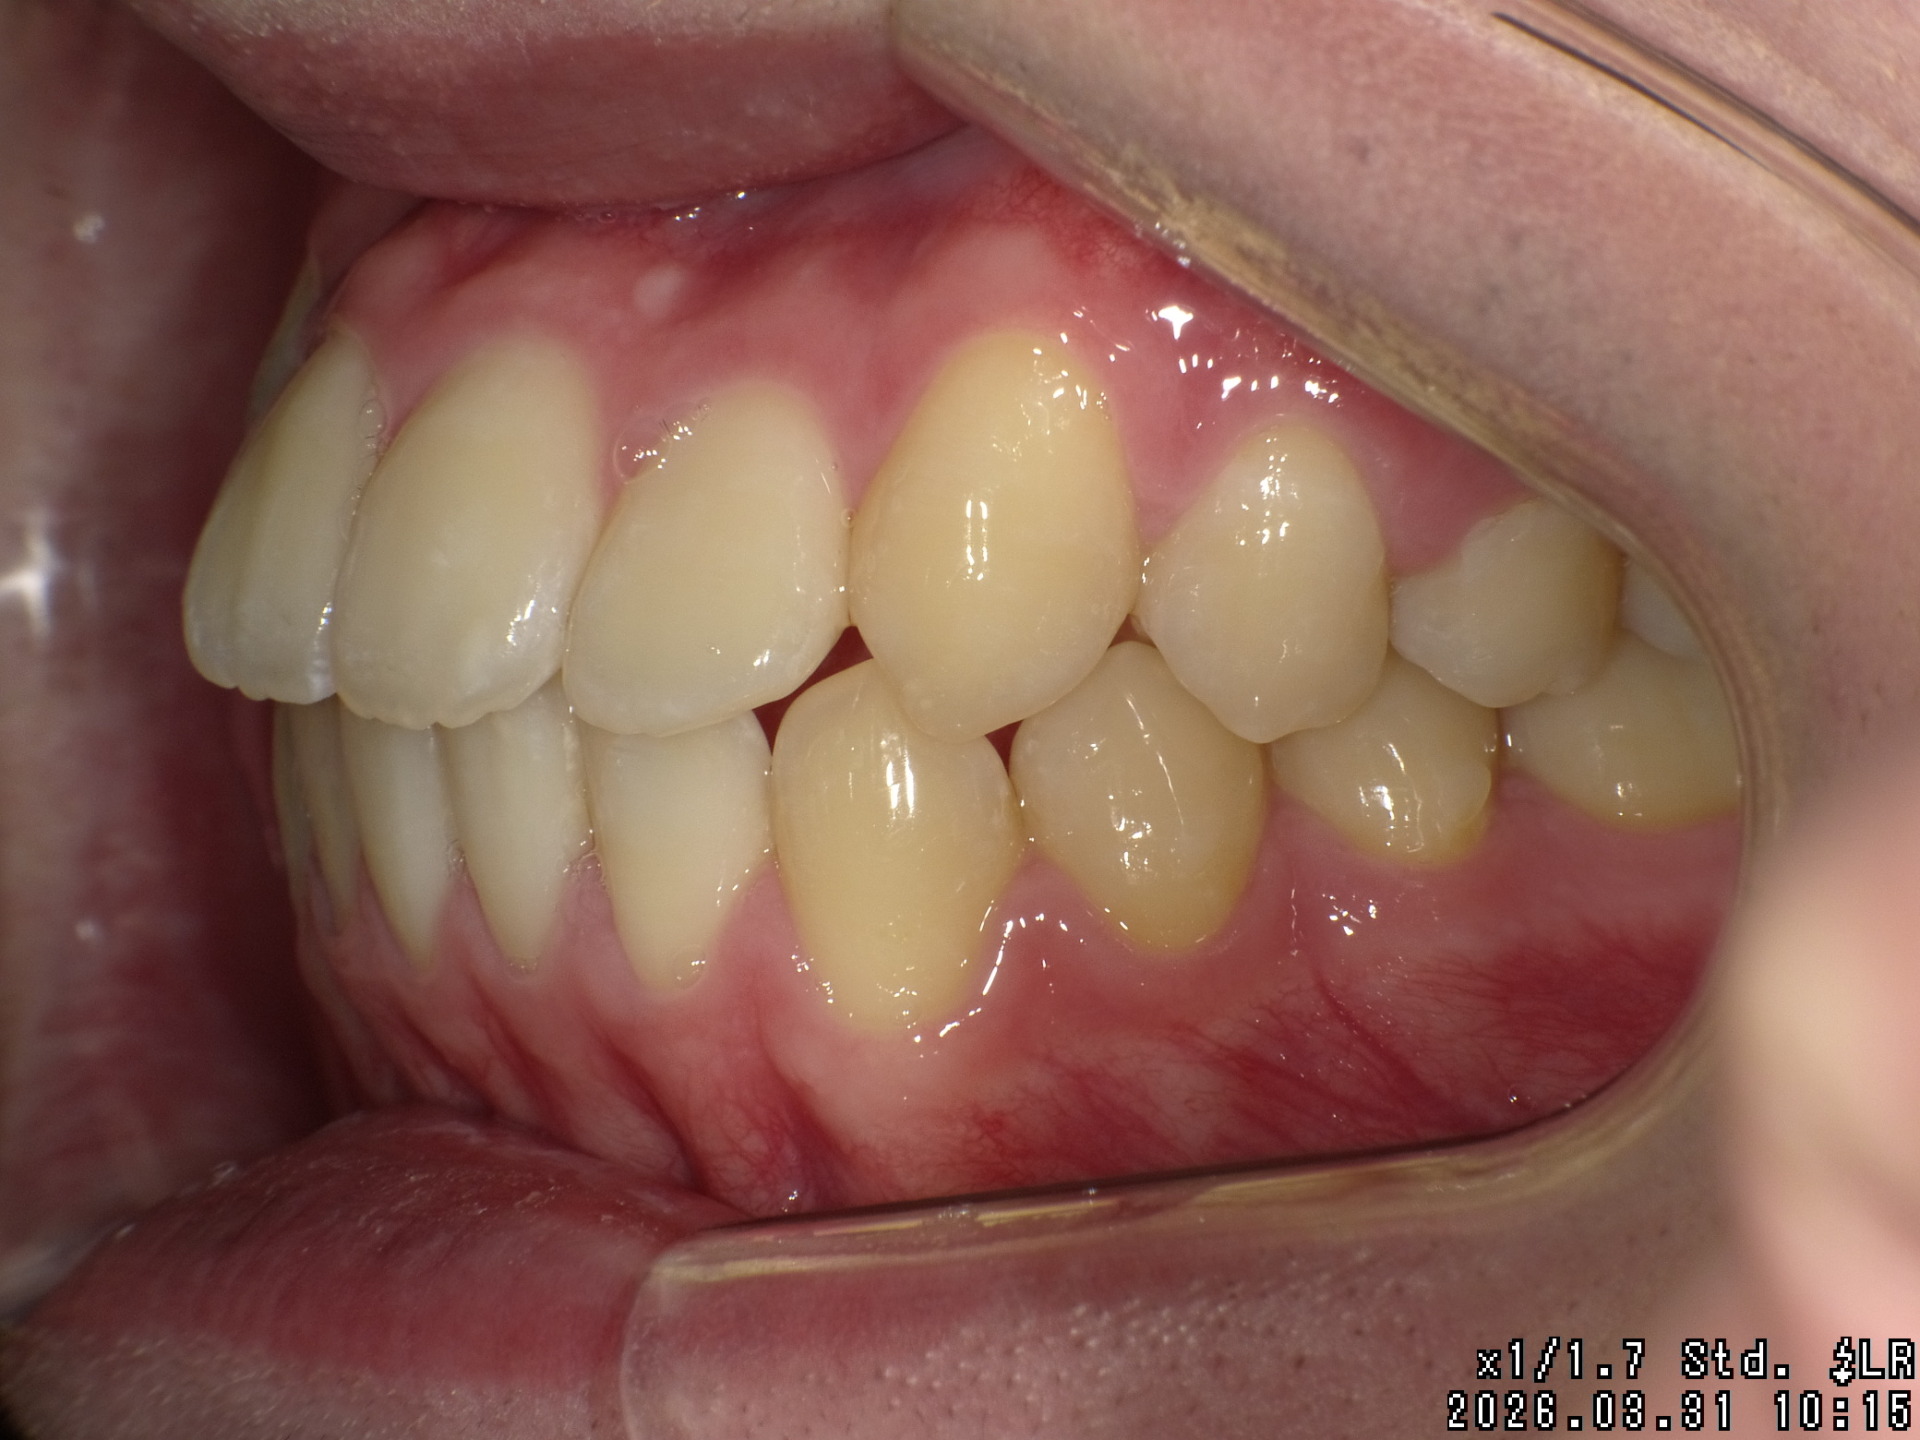

After